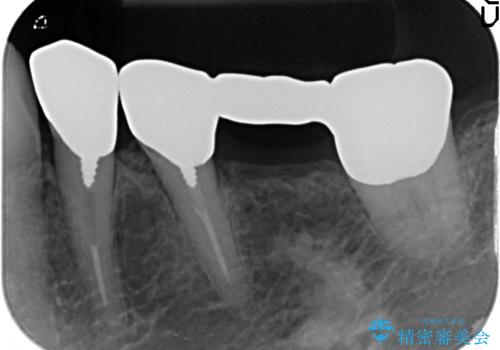

- 古くなり黒ずんできたブリッジのやりかえを希望され来院されました。

老朽化した銀パラジウム合金のブリッジを除去し、ジルコニア製のブリッジでやりかえを計画します。